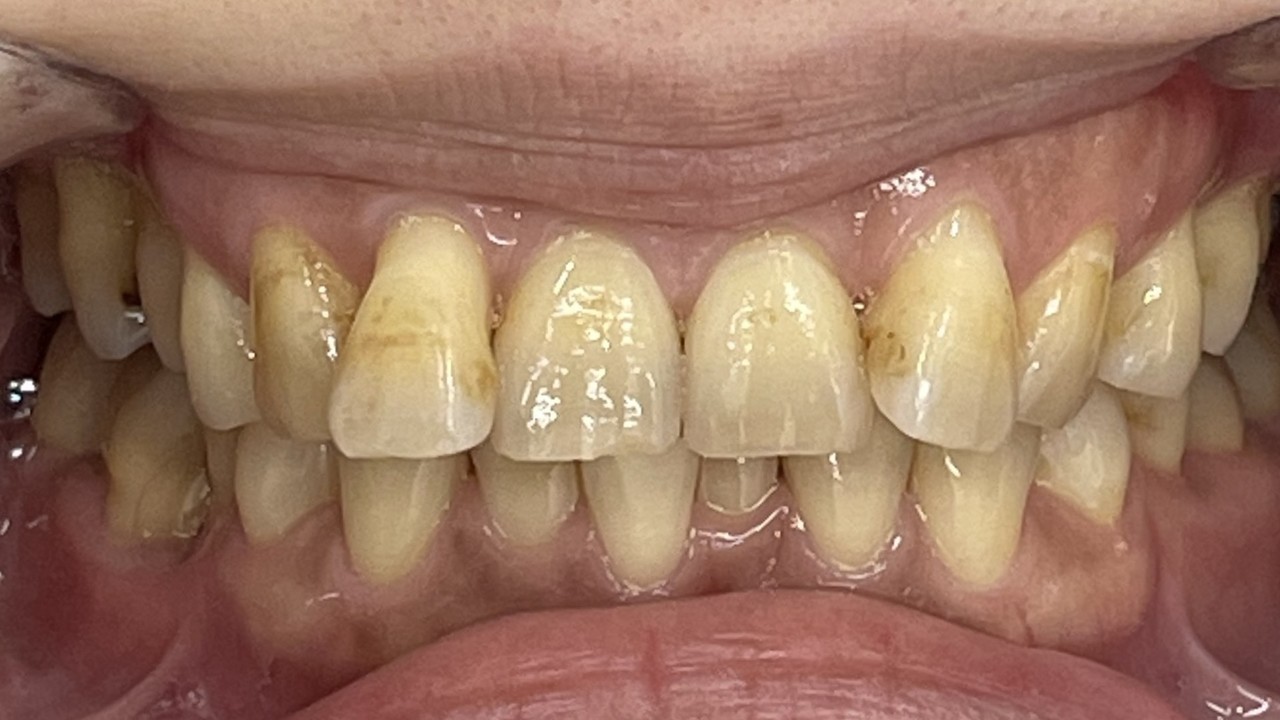

Before

After

矯正の種類 / invisalign GO

年齢・性別 / 50代女性

主訴  /  叢生 交叉咬合

治療期間 / 17ヶ月

費用 / 簡易検査 5,000円(税別) 精密検査 30,000円(税別)

両額マウスピース 450,000円(税別)  両額リテイナー料 60,000円(税別)

※マウスピース交換時別途調節料3,000円(税別)

副作用 / 口内炎・歯の移動に伴う痛み・知覚過敏 ※数日で収まる場合が多いです

リスク / 後戻り防止の為、夜のみマウスピースで保定を指示